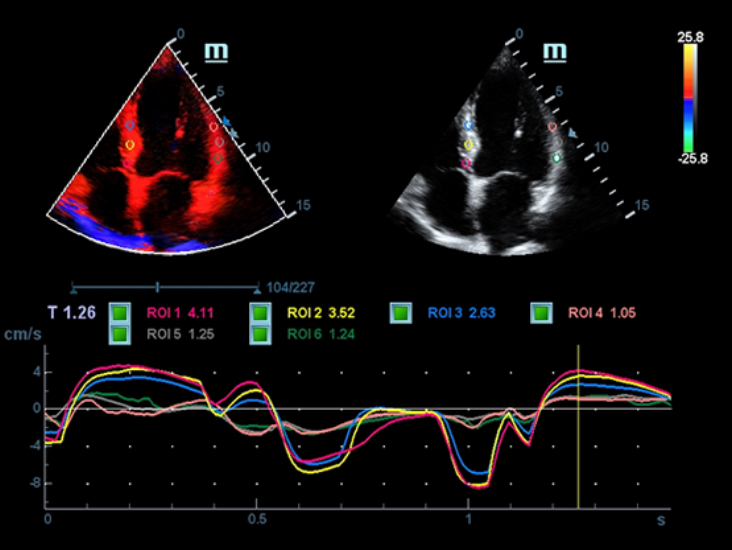

Специализированный уход благодаря ECHO

Многофункциональная система DC-60 Exp с X-Insight представляет собой комплексное решение, которое помогает управлять повседневной клинической практикой с легкостью и уверенностью.

Основываясь на глубоком понимании потребностей клиентов, компания Mindray разработала систему DC-60 Exp с X-Insight, чтобы обеспечить высокую производительность и точность визуализации вкупе с наглядностью, исключительной интеллектуальностью и огромным опытом.

Опыт работы и высокая производительность